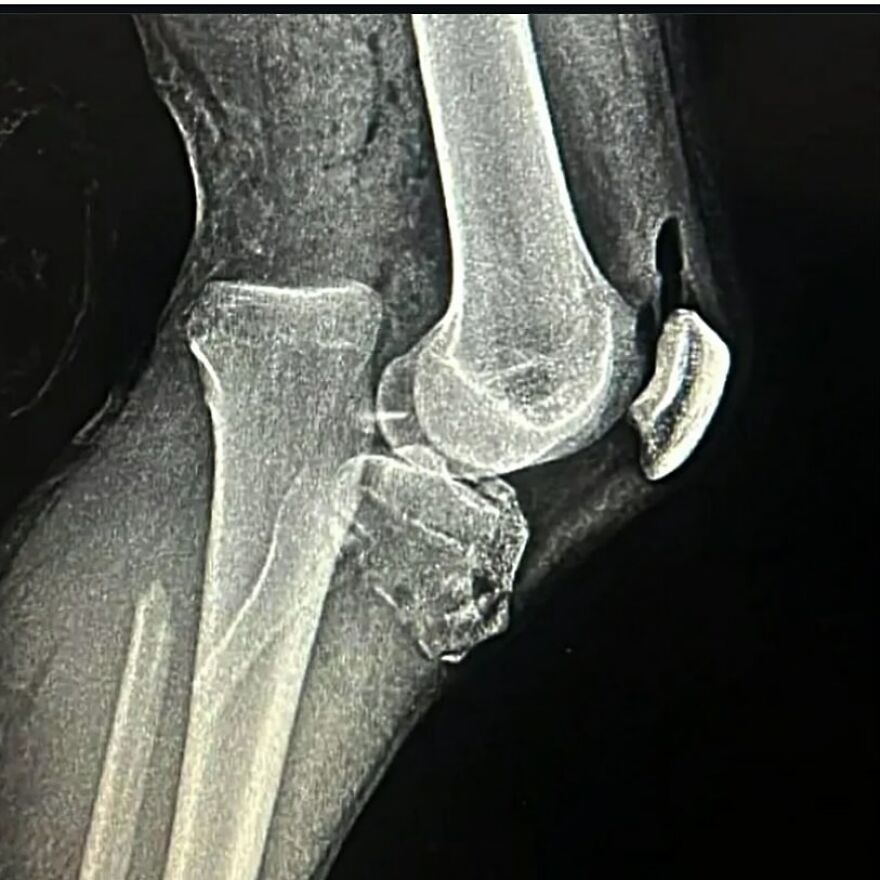

Looks like another" feet on the dashboard" of a car involved in an accident

The only thing I can dig up is "A man in his 50's, while under the influence, fell onto the pedal of his bicycle".